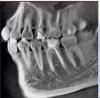

Гость Vini Vidi Vici Опубликовано 26 июля, 2008 Поделиться Опубликовано 26 июля, 2008 (изменено) Я, понимаете ли, не стоматолог. Пальцем в небо - не хочется. По поводу разъясненной верхней 6-ки - поняла, что можно жить и так, раз уж не беспокоит (пока?), а можно и переделать. Опять же мнение - перепломбировка нежелательна, если необязательна. А кто скажет, обязательна ли? Выходит, никто. А вот по поводу нижней как раз ничего не понятно, потому как повода для боли вроде как и нет, а боль есть, и не первый день. Я терпеть могу, к счастью болит в основном при воздействии, и в ухо стреляет. Жить и питаться можно. НО не хочется запустить то, что можно вылечить. Кроме того несколько вопросов озвучила выше - насчет горячей гуттаперчи при перепломбировке, и предпочтительности лечения во время или после обострения. Спасибо.А на 7 верхнем пломба давно стоит? Может быть и пульпит 27. Снимочек 26 не информативен, к сожалению. Изменено 26 июля, 2008 пользователем Vini Vidi Vici Ссылка на комментарий

zybnaya feya Опубликовано 28 июля, 2008 Поделиться Опубликовано 28 июля, 2008 Пломба стоит меньше года, пульпит подозревали, но по результатам проверки током (простите, не знаю термина) сказали - нет его. Хотя зуб реагирует на холодное. Списали на оголенную шейку. Спасибо всем! Вам перелечивать надо как нижний моляр,так и верхний. В обоих зубах каналы недопломбированы до верхушки-отсюда и все беспокойства. Горячая гуттаперча-идеальный вариант,даже не сомневайтесь. Ссылка на комментарий